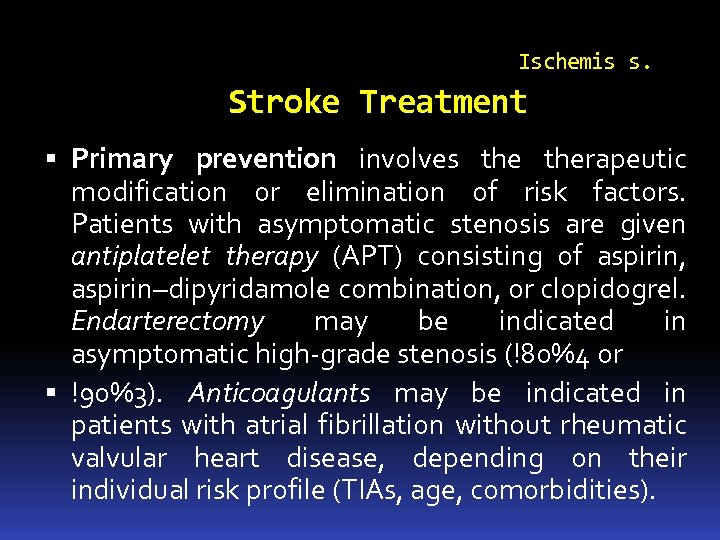

Ischemis s. Stroke Treatment Primary prevention involves therapeutic modification or elimination of risk factors. Patients with asymptomatic stenosis are given antiplatelet therapy (APT) consisting of aspirin, aspirin–dipyridamole combination, or clopidogrel. Endarterectomy may be indicated in asymptomatic high-grade stenosis (!80%4 or !90%3). Anticoagulants may be indicated in patients with atrial fibrillation without rheumatic valvular heart disease, depending on their individual risk profile (TIAs, age, comorbidities).

Ischemis s. Stroke Treatment Primary prevention involves therapeutic modification or elimination of risk factors. Patients with asymptomatic stenosis are given antiplatelet therapy (APT) consisting of aspirin, aspirin–dipyridamole combination, or clopidogrel. Endarterectomy may be indicated in asymptomatic high-grade stenosis (!80%4 or !90%3). Anticoagulants may be indicated in patients with atrial fibrillation without rheumatic valvular heart disease, depending on their individual risk profile (TIAs, age, comorbidities).